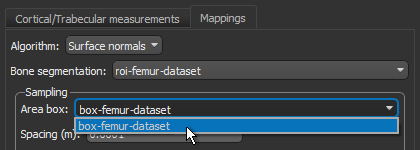

- Do the following on the Mappings tab:

- Choose Surface normals in the Algorithm drop-down menu.

- Choose the region of interest that you created for this tutorial in the Bone segmentation drop-down menu.

- Choose the box that encloses the area that you want to include in your analysis in the Area box drop-down menu.

- Enter a value of 0.002 m in the Spacing edit box.